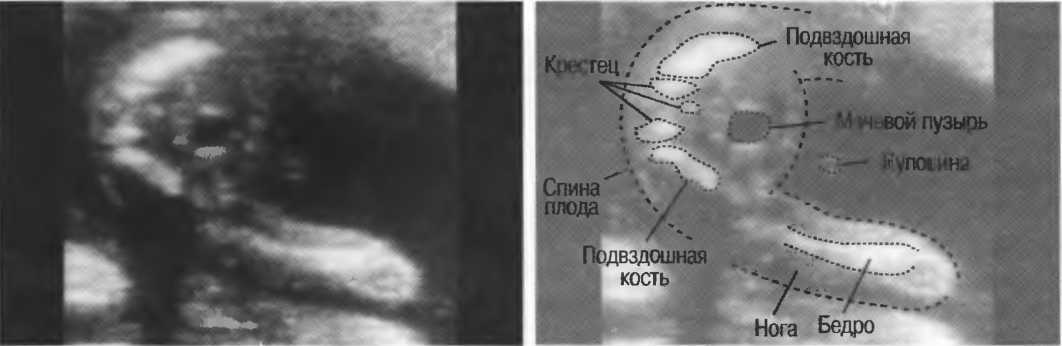

Рис.5. Два поперечных среза плода, демонстрирующих тень от позвоночника плода. Аналогичная тень от ребер может частично закрывать почки или печень. Изменяя угол наклона датчика, можно изменить положение тени таким образом, чтобы подлежащие ткани были видны отчетливо.